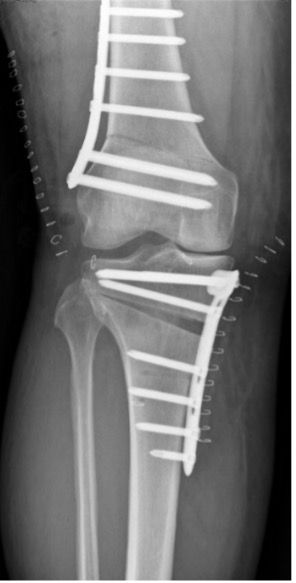

One of the central questions is how far the proximal metaphyseal tibia angle may be changed, or how much joint line obliquity (JLO) can be tolerated. For Song [29], the limit of the MPTA is between 94 and 96°. Corrections with a greater angle have poorer long-term outcomes. However, Akamatsu [30] reports good short-term results in corrections of more than 95° MPTA. If the extent of the corrections is so large that the critical medial proximal tibia angle is exceeded (MPTA >94°) or there is already a JLO >4° during planning, then double osteotomy is the therapy of choice; we then correct the femur first (lateral closing wedge) and can then adjust the tibia correction somewhat (Fig. 9b).